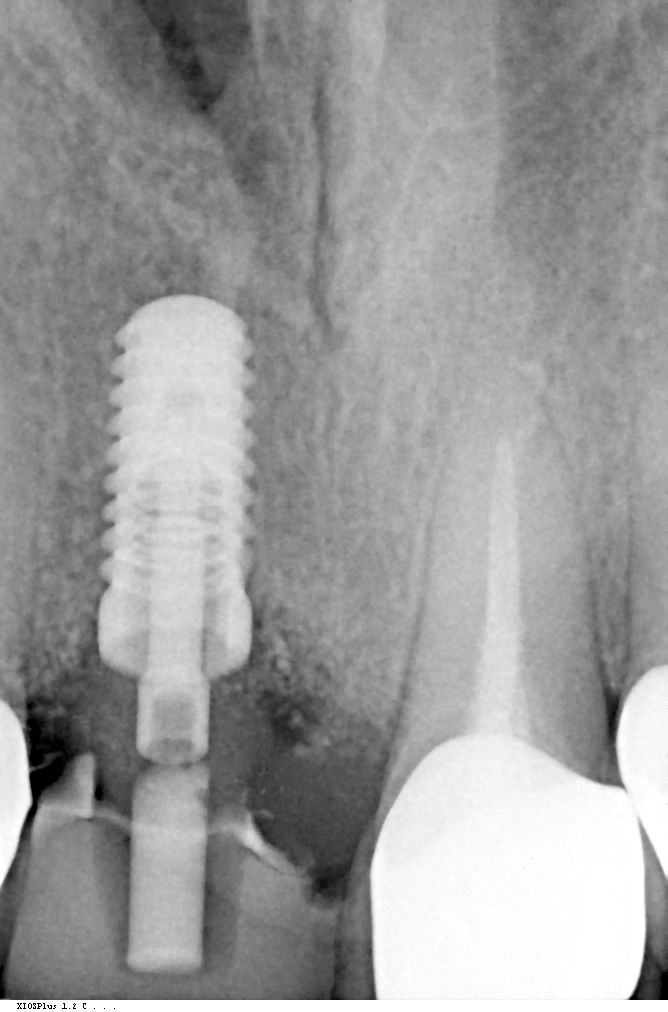

Verwendet wurde im vorliegenden Fall das Implantatsystem Procone (Medentika). Die Aufbereitung des Implantatbettes regio 11 erfolgte nach Bohrprotokoll bis zum Durchmesser 4,3 mm. Der Spalt zum fazialen Knochen wurde mit einem bovinen Augmentat (Cerabone, Straumann) gefüllt. Zur verbesserten Wundheilung sind sowohl das Implantat als auch das Cerabone vor dem Einsetzen mit patienteneigenem Blutplasma bzw. Wachstumsfaktoren (iPRF) benetzt worden (Abb. 7 und 8). Das Implantat wurde nach dem Gewindeschneiden palatinal orientiert inseriert, sodass der Einbringpfosten bukkal hinter der fazialen Fläche der Nachbarzähne platziert war. Der Verschluss erfolgte erstmal mit einer Einheilkappe (Höhe 2 mm) (Abb. 9).

Eine radiologische Kontrolle bestätigte die Ossifikation des Implantats. Nach der Eröffnung der Situation konnte die unter der Gingiva liegende Einheilkappe (2 mm) regio 11 gegen eine höhere Einheilkappe (4 mm) ausgetauscht werden. Ziel war es, das Weichgewebe zu konditionieren und eine gute Basis für ein natürliches Emergenzprofil zu schaffen. Zehn Tage später wurde die Situation mit Abformpfosten und offenem individuellem Löffel abgeformt (Impregum, 3M). Das Implantat wurde mit einem provisorischen Abformpfosten aus PEEK versorgt und eine Chairside gefertigte provisorische Krone eingegliedert. Die Herstellung der definitiven implantatprothetischen Versorgung erfolgte im Dentallabor. Nach einer Woche konnte die provisorische Restauration entfernt und die keramische Implantatkrone mit Carboxylatzement (Durelon, 3M) zementiert werden (Abb. 15 und 16). Hierbei wurde auf die gründliche Entfernung der Zementreste geachtet und die saubere Fuge im Röntgenbild nochmals geprüft. Mit der implantatprothetischen Restauration ist der Patient in ästhetischer sowie funktioneller Hinsicht sehr zufrieden (Abb. 17 und 18).